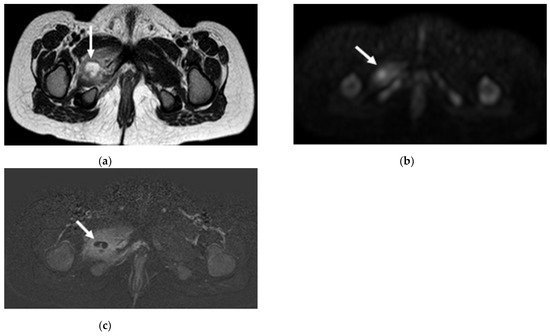

3.3. Radiologic Investigations

- Khoo, M.M.Y.; Tyler, P.A.; Saifuddin, A.; Padhani, A.R. Diffusion-weighted imaging (DWI) in musculoskeletal MRI: A critical review. Skelet. Radiol. 2011, 40, 665–681. [Google Scholar] [CrossRef]

- Kumar, J.; Khaleel, M.; Boothe, E.; Awdeh, H.; Wadhwa, V.; Chhabra, A. Role of Diffusion Weighted Imaging in Musculoskeletal Infections: Current Perspectives. Eur. Radiol. 2016, 27, 414–423. [Google Scholar] [CrossRef]